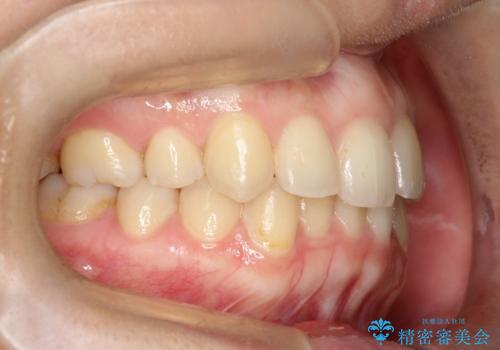

矯正後の後戻り インビザラインで改善

- 20代女性

- 矯正装置

- 治療期間

- 7ヶ月

- 前歯のガタツキが気になると来院されました。

マウスピース矯正治療を選択しました。